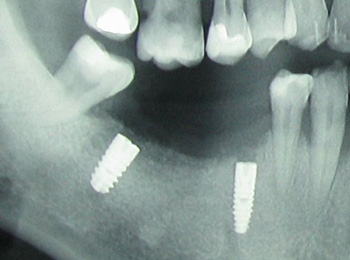

IMPLANTATI ![]()

Implantologija je sodobno nadomeščanje izgubljenih zob s titanskimi zobnimi vsadki, ki v bistvu nadomeščajo korenine izgubljenih zob. Že pomanjkanje enega zoba močno vpliva na funkcijo celotnega žvečilnega sistema in lahko precej uniči estetiko. Vsadek rešuje obe težavi brez brušenja sosednjih zob. Čeprav obstajajo številne tehnike s katerimi lahko nadomestimo manjkajoče zobe, nobena ni tako funkcionalna in vzdržljiva kot vsadek. Vsadek zagotavlja najbolj naraven prenos sil in na mestu manjkajočega zoba preneha izguba kostne mase (kar je normalno po izgubi zob). Vsadki se ne uporabljajo le pri izgubi enega zoba, ampak tudi v povezavi z drugimi protetičnimi rešitvami. Tako jih zelo uspešno uporabljamo v brezzobi čeljusti, kjer so lahko nosilci mostu pri pacientih, ki bi sicer morali uporabljati mobilne proteze. Vsadek je lahko tudi sidro za totalno protezo, ki zagotavljata njeno stabilnost in omogoča pacientu prijetno in varno delovanje.

Postopek vsaditve

Vgraditev implantata se izvaja v lokalni anesteziji. Postopek je popolnoma neboleč. V izbrano lokacijo v kosti se vgradi titanov vijak, ki se pusti 3-6 mesecev, da zraste s kostjo. Postopek se imenuje oseointegracija in je nujno potreben za stabilnost in trajnost implantata. Vsadki so narejeni iz titana, ki spodbuja celice okoli vsadka, da ustvarijo novo kost. Po obdobju oseointegracije, se implantat odpre in se s pomočjo posebnega elementa oblikuje zobno meso, ki daje naraven videz. Ta postopek traja 2-4 tedne, potem se izdeluje nekaj podobno kroni naravnega zoba.